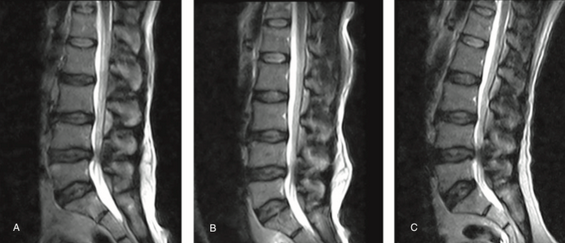

腰椎滑脱Meyerding分级